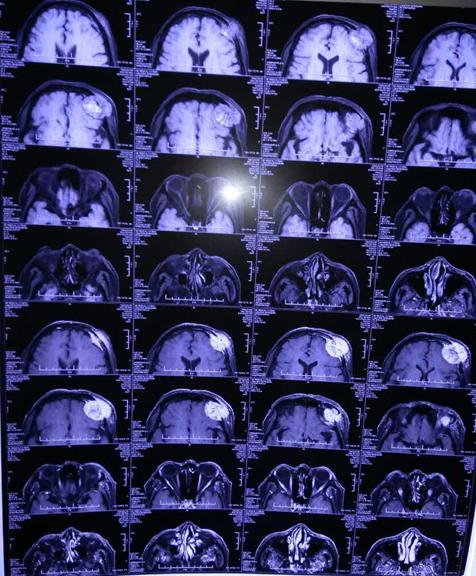

第四军医大学唐都医院神经外科五病区贾栋主任门诊仔细为李大爷进行查体,了解患者病史后建议首先进行影像学检查,后经头颅MRI显示:患者左侧额部可见一大小约4.3CMX4.2CMX3.5CM包块,呈稍长T1,稍长T2信号,其内可见点片状短T1,长T2混杂信号影,病变与邻近脑膜关系密切,邻近颅骨呈溶骨性骨质破坏,并突破颅骨向外生长及向眶内生长,左侧上直肌受压,左侧额叶受压,病变与额叶间可见弧形长T2脑脊液信号影,确诊为脑膜瘤,建议尽快进行手术治疗。

患者影像学资料: